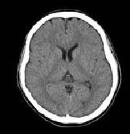

脳卒中では一般写真では見ることができない出血の広がりや場所を画像としてみることができます。また、造影剤を使用することによりくも膜下出血の原因である動脈瘤の位置を特定できることもあります。

がんに対してもCT検査は有用で、短い時間で広い範囲を撮影できるので、呼吸によるブレも少なく、がんの大きさや形まで見ることができます。また、造影剤を使用することにより病変の性状まで知ることができます。

マルチスライスCTは全身を高速で高分解能に撮影できる利点があり、10秒程度の息止めで胸部から腹部までの撮影が可能です。特に、造影CT検査では造影剤を急速に注入することによってダイナミックCTや3D-CTアンギオが容易に施行可能です。